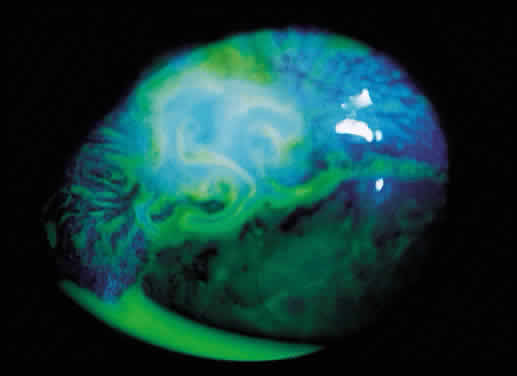

Hypotony (i.e., IOP less than 6 mmHg) after glaucoma surgery can result from excessive aqueous outflow (related to excessive filtration [see later], wound leak, or cyclodialysis cleft) or to reduced aqueous production (related to ciliochoroidal detachment, inflammation, inadvertent use of aqueous suppressants, or extensive cyclodestruction).9 These conditions can coexist. For example, low IOP from overfiltration can induce ciliochoroidal detachment and secondary decreased aqueous production. Possible complications include flat anterior chamber, gradual failure of the bleb, visual loss, cataract, corneal edema, Descemet's membrane folds, choroidal hemorrhage, macular and optic disc edema, and chorioretinal folds (predominantly in young myopic patients). According to Spaeth (Table 1),10 the severity of flat anterior chamber can be classified as grade I when there is peripheral-iris apposition, grade II with pupillary border-corneal apposition, or grade III with lens-corneal touch (see Chapter 15). The central anterior chamber depth also can be described relative to the corneal thickness. Choroidal effusion occurs when fluid collects in the suprachoroidal space (Fig. 2), resulting in forward movement of the lens iris diaphragm with anterior chamber shallowing. On fundus examination, moundlike elevations of the choroid, more commonly in the periphery, are visible.

The initial management of early postoperative hypotony with a formed anterior chamber is conservative. Topical steroids and cycloplegics are used. Restrictions in activity (bending, weight lifting) and avoidance of Valsalva-positive conditions are recommended, especially in patients at risk for suprachoroidal hemorrhage (see earlier). If there is hyposecretion related to intraocular inflammation, ciliochoroidal detachment, or both, the initial treatment consists of intense corticosteroid therapy and long-acting cycloplegics, which stabilize the blood-aqueous barrier. Intervention is indicated in patients with hypotony associated with other complications and in persistent, low IOP with loss of visual acuity and hypotony maculopathy. After filtration surgery, prompt management is indicated, also when there is loss of bleb height. Treatment should be aimed at correcting the specific cause of hypotony. When there is lens-corneal touch (flat anterior chamber, grade III) immediate surgical intervention is necessary to prevent endothelial damage and cataract formation (see Chapter 15). Reformation of the anterior chamber with air, balanced salt solution, or, preferably, a viscoelastic can be done at the slit lamp or under the operating microscope through the paracentesis made intraoperatively. Viscoelastic material is best for maintaining, at least temporarily, the anterior chamber depth. When there are large and appositional choroidal effusions, drainage of the fluid also is necessary (Fig. 4). The technique is described in detail in Chapter 15.